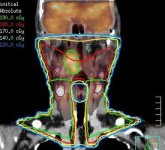

多形態圖像自動配准

Syntegra多模配准軟體能夠自動將生理學影像(如PET等)與解剖學影像(CT或MR)相匹配,使臨床醫生無需手動調整和匹配影像。 這一即時影像配准能夠協助進行腫瘤確認,從而縮短了放射治療計畫流程,為您帶來更強的診斷信心。 Syntegra通過使用快速的交互資訊、交叉相關和局部相關等演算法,提高其快速、可重複的自動三維配准的準確性。 無論是何種診斷性影像PET、CT和MR,或者其他放射腫瘤影像,用戶都能夠選擇最適合其特定臨床應用的最佳演算法。